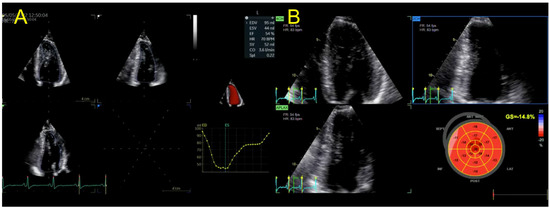

| Echocardiography | Hypokinetic non-dilated cardiomyopathy LVEF = 42% Mild mitral regurgitation IAS aneurysm | Hypokinetic non-dilated cardiomyopathy LVEF = 34% Mild mitral regurgitation IAS aneurysm | Left ventricular concentric hypertrophy LVEF = 54% |